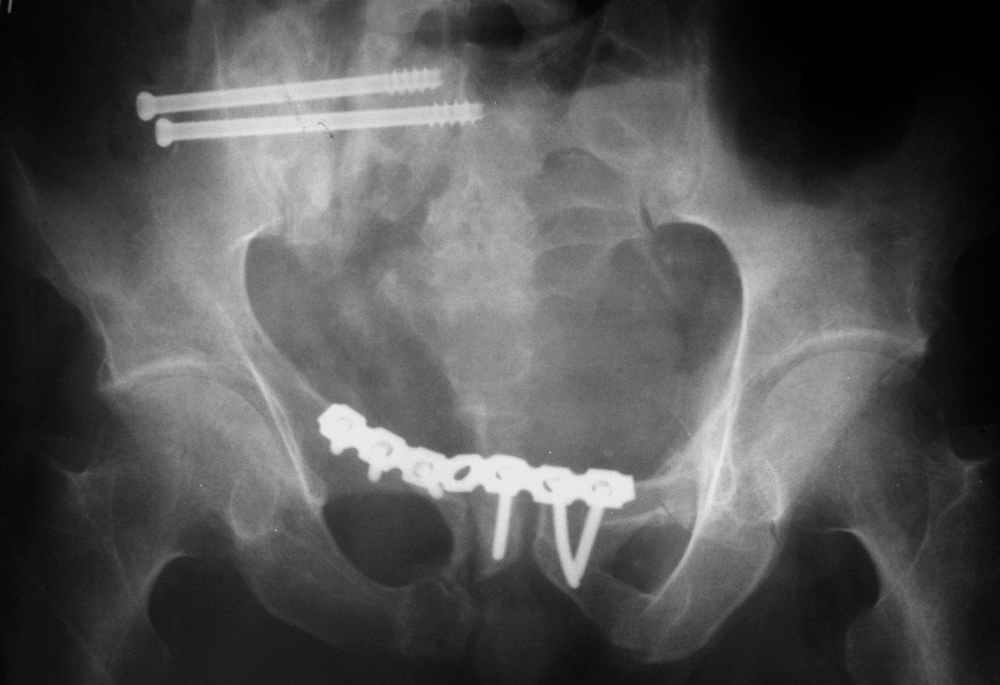

Уважаемые коллеги!Прошу помочь определиться с тактикой лечения пациента 23 лет со сросшимся со смещением вертикальным переломом таза.Заранее благодарю,Виталий Евгеньевич Казеннов, Хабаровск Извлечения из выписного эпикризаБольной Л. М. В., 23 лет, находился на лечении во Взрослом ортопедическом отделении № 2 Краевой больницы № 2 г.Хабаровска с 28 августа 2004 г. по 25 октября 2004 г. с диагнозом: Автотравма 25.07.04 г. Закрытый несвежий осложненный оскольчатый перелом задней колонны и крыши вертлужной впадины справа с задним подвывихом головки бедренной кости. Травматический неврит седалищного нерва справа на уровне тазобедренного сустава с выпадением функции (до пареза) малоберцовой порции. Закрытый вертикальный перелом боковых масс крестца справа со смещением правой половины таза кверху. Срастающийся перелом с/3 правой бедренной кости, фиксированный интрамедуллярно стержнем. Ранний восстановительный период ЗЧМТ.01.09.04 г. Открытая репозиция перелома правой вертлужной впадины, невролиз седалищного нерва, накостный остеосинтез реконструктивной пластиной. Чрескостный остеосинтез костей таза спице-стержневым аппаратом внешней фиксации <таз-бедро>. 25.10.04 Зав. отделением: Сапежников В.А. Врач: Шершнев М.В.

По прямой проекции - Вертикальная стабильная (?) деформация таза IIIст., неправильно сросшийся (?) перелом боковой массы крестца справа, неправильно сросшийся поперечный (?) перелом првавой вертлужной впадины.

Реконструктивная "пластина" очень напоминает трафарет, а не пластину с винтами?! Конгруентность в суставе непонятна.

окончательная фиксация